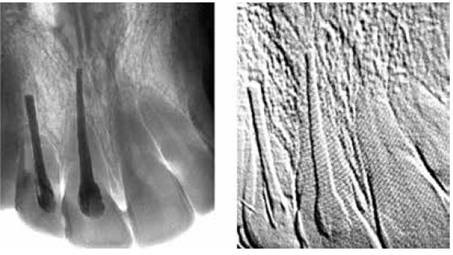

• Base Microbiológica de las Caries Dental

Base Microbiológica de las Caries Dental

Alemania, Willoughby Miller establece la base microbiológica de las caries dentales e inicia la discusion de lo que sera la "infeccion focal" descubriendo las bacterias de la pulpa dental.